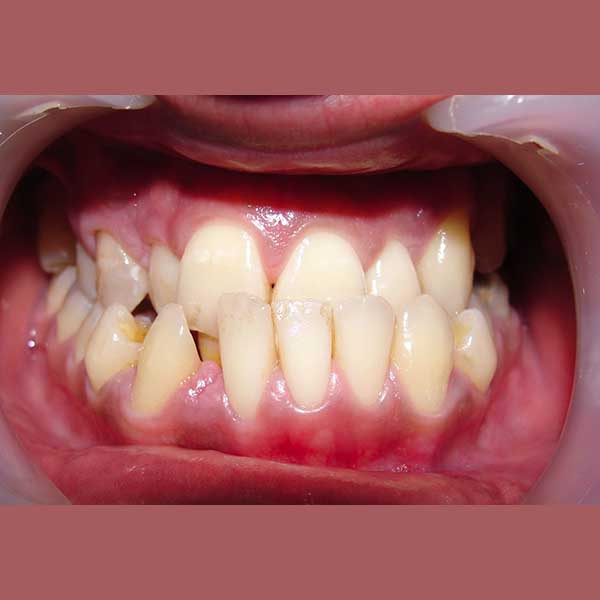

AFTER

ولحسن الحظ في حالتها كان بالإمكان اجراء المعالجة من دون قلع أسنان، وقد اخترت استخدام التقويم ذاتي الربط (تقويم الدايمون) لأنه يساعد في تحريك الأسنان وتوسيع الفكين. وبالفعل، في نهاية العلاج نجحنا في رصف الأسنان بشكل ممتاز، وبات بإمكان مراجعتنا الابتسام بثقة وسعادة مجدداً.